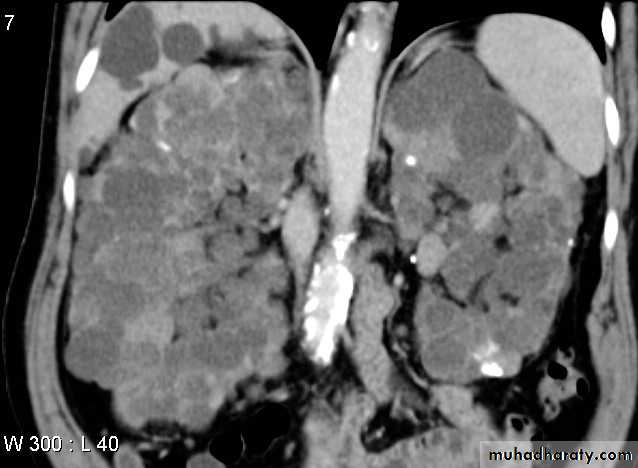

Polycystic renal disese in CT scan diffuse liver & kidney affection